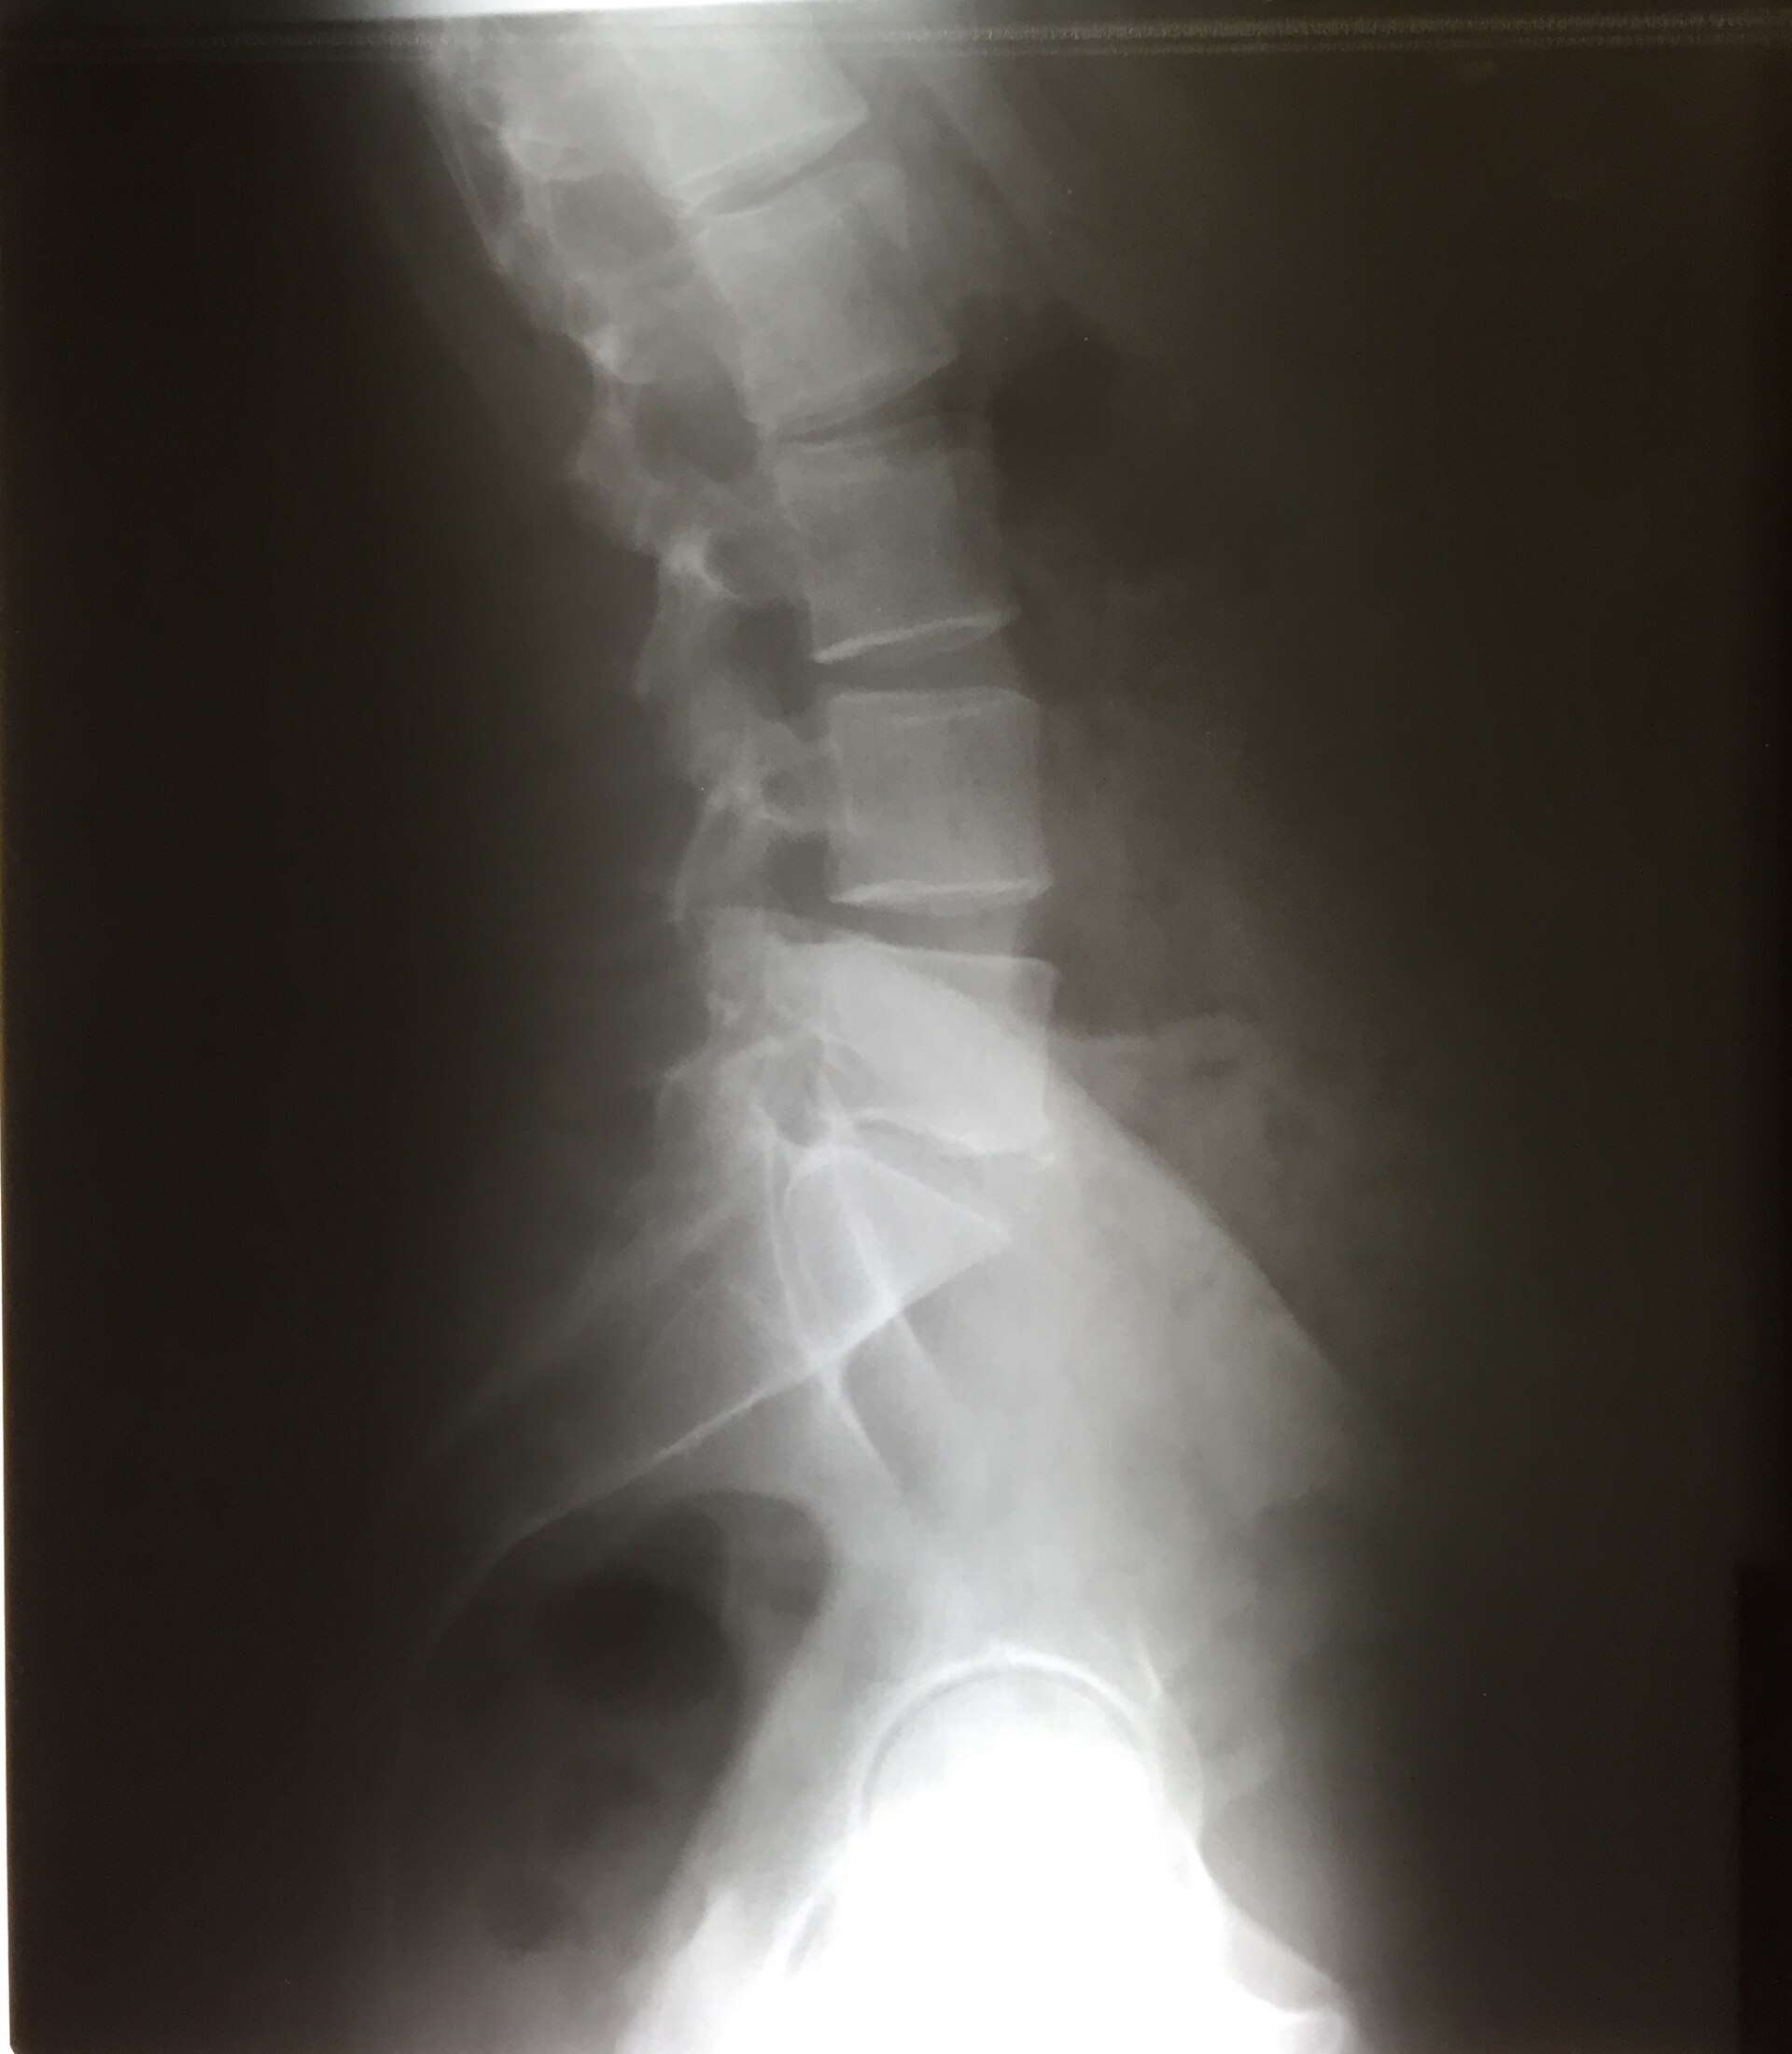

Anteroposterior radiograph of the lumbar spine.